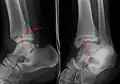

On X-rays, there can be a fracture of the medial malleolus, the lateral malleolus, and/or of the anterior/posterior margin of the distal tibia. The posterior margin (known as the posterior malleolus) is much more frequently injured than the anterior aspect of the distal tibia. If both the lateral and medial malleoli are broken, this is called a bimalleolar fracture (some of them are called Pott's fractures). If the posterior malleolus is also fractured, this is called a trimalleolar fracture.

A triplane fracture of the ankle as seen on plain X-ray